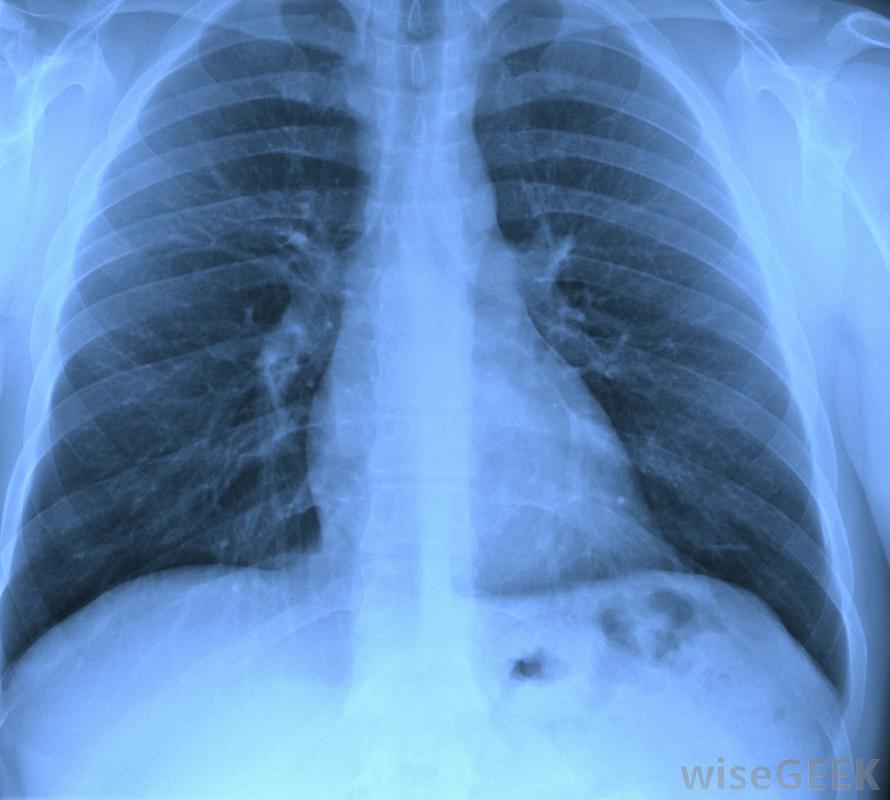

持续咳嗽可能是肺癌的症状持续咳嗽的原因一般都有一个共同点,都是因为肺部有东西阻塞了呼吸道,导致咳嗽,这是人体试图消除阻塞的方式。大多数咳嗽的原因都是暂时的,如因感冒或短暂吸入烟雾而引起的胸部充血。持续咳嗽通常是由更严重的情况引起的,如肺部有大量焦油或粘液或吸入

哮喘可能会导致持续咳嗽某些疾病,如哮喘,也可能引起持续的咳嗽。肺病是另一种可能,也是某些癌症的一种。事实上,慢性和严重的咳嗽是肺癌的主要症状之一,它可能伴有胸部疼痛和喘息,虽然有时在诊断时没有症状。反流或食物吸入肺部也可能导致持续咳嗽。有时这可以通过饮食和药物治疗,咳嗽可能平息。其他时候可能需要手术,或者食物和饮料需要加厚以防止它再次进入呼吸道。任何时候咳嗽持续超过一到两周,主要是如果病情严重,并伴有粘液或胸痛,应咨询医生,排除严重的疾病。很多时候,有一个简单的解释,例如由于环境原因导致的长期过敏。在一些罕见的情况下,可能是一种潜在的危及生命的疾病,治疗需要迅速开始。